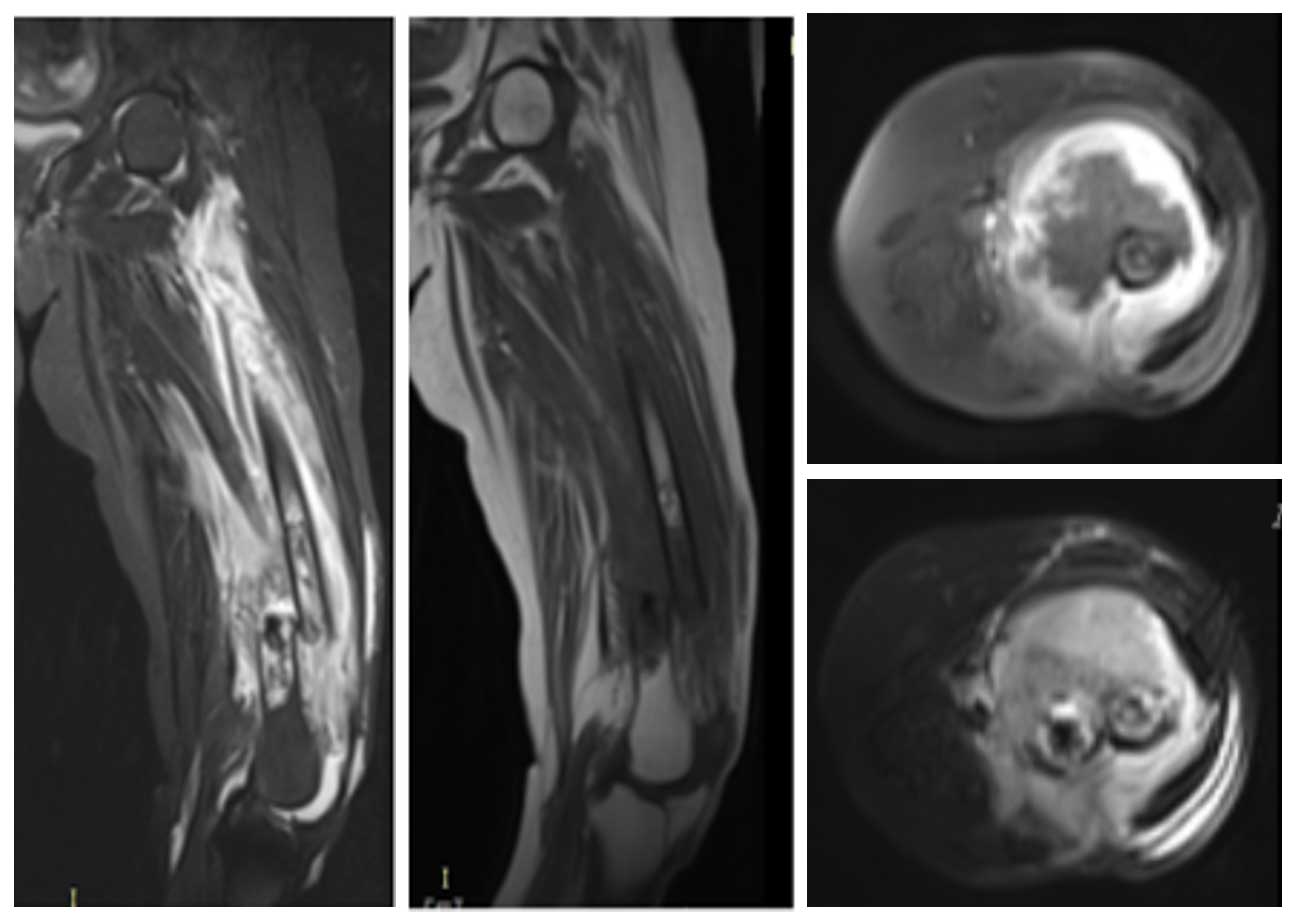

Ameliyat Öncesi: MR’da ek olarak çevreleyen yaygın ödem görülmekte.